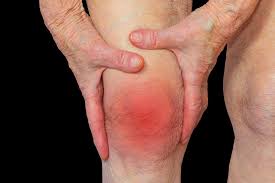

날씨가 급격히 추워지면서 관절통증을 호소하는 사람들이 늘고있다고 한다.

특히 통증이 심한 류마티스관절염은 자가면역질환 중 하나로, 관절에 만성적 염증과 통증을 일으켜 결국 비가역적인 관절손상을 일으키는 질환이라고 한다.

원장은 “특히 겨울철에는 증상이 더욱 심해지는 경향이 있는데, 기온이 내려가면서 관절 주위의 근육이나 인대, 힘줄들이 추위로 인해 수축되어 더욱 뻣뻣해지기 때문이다라고 한다.